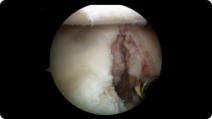

Arthroscopic image of a miniscus tear Arthroscopic image of a miniscus tear after knee arthroscopy

After Knee Arthroscopy